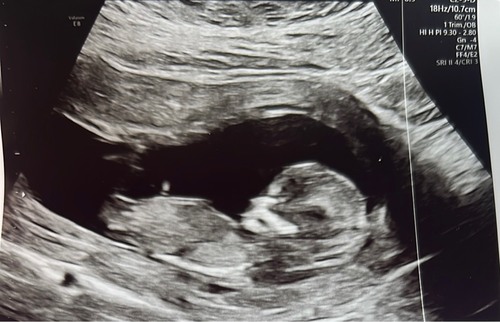

Deel hem hier nog een keer omdat er net een nieuw topic is geopend. 🩷 of 🩵 ?

Ik denk een meisje.